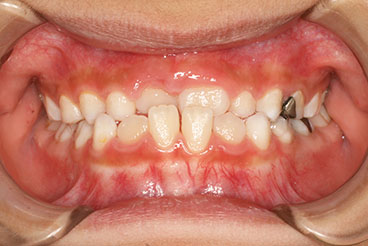

受け口を気にされ、他院からの紹介で来院された患者さんです。

小学2年生、生え変わりの時期から小児矯正を開始しました。

小児矯正で前歯の咬み合わせを改善し、

永久歯列完成後の中学生から非抜歯治療にて本格矯正を開始。

配列し仕上げました。